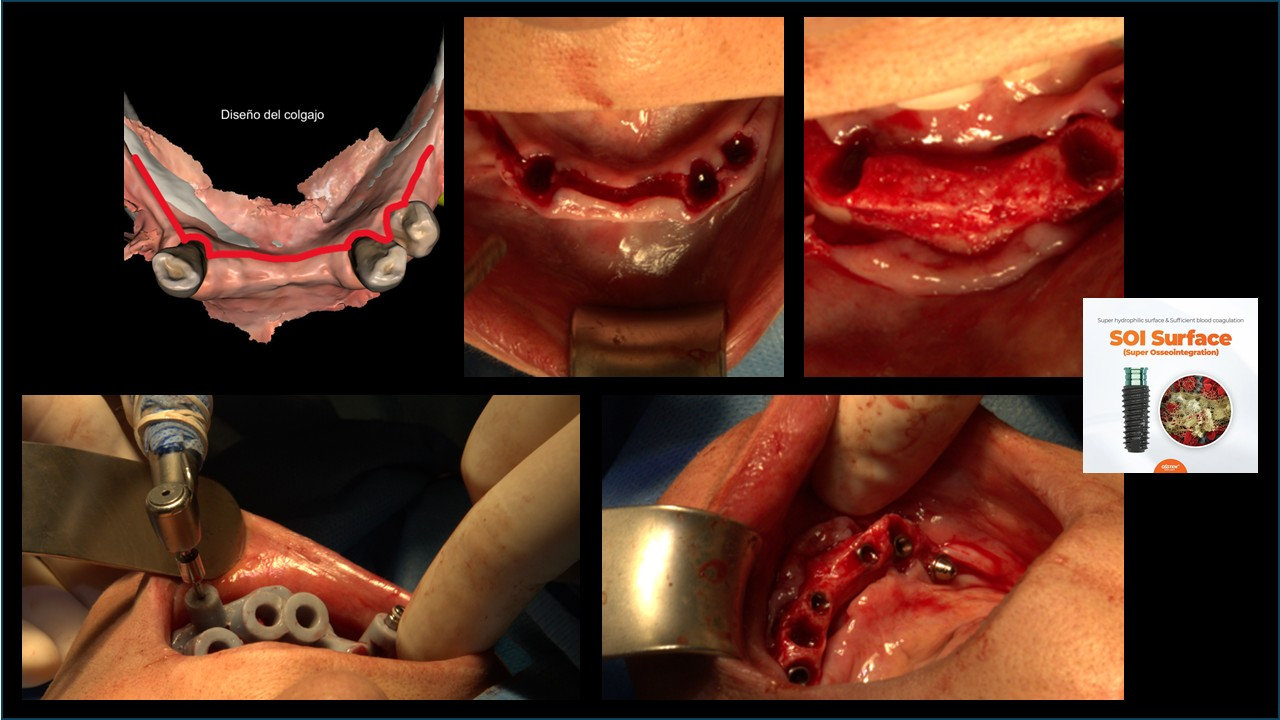

Técnica:

• Exodoncia dientes 4.3, 3.3 y 3.4.

• Colgajo espesor total en grupo V.

• Instalación de guía CX para desgaste de reborde óseo.

• Instalación de guía CX para posicionamiento de IOI (posiciones 4.5, 4.3, 4.1, 3.3, 3.5).

• Regeneración ósea guiada en relación a reborde óseo y alveolos de exodoncias. Cierre con membrana colágeno.

• Prueba de estabilidad primaria en IOI que serán cargados.

• Instalación de pilares multiunit en IOI que serán cargados. Prueba de coincidencia con pilares temporales en provisorio.

• Implantes dentales Osstem TSIII Superficie SOI Ø4.0x8.5mm (#1), Ø4.0x10mm (#5), Ø3.5x10mm (#2, #3, #4).

• Aloinjerto "Allo Oss", 1cc.

• Membrana de colágeno "OssGuide", 20*30mm (2).